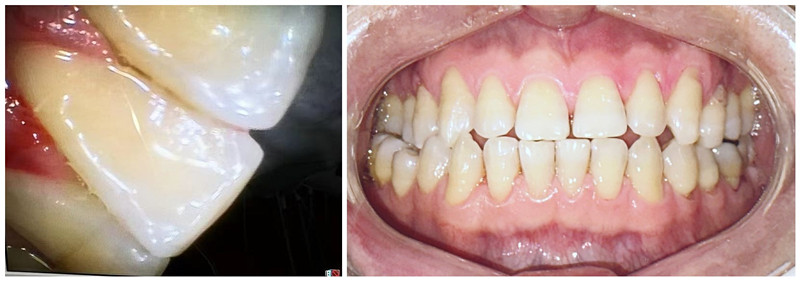

陈女士近日刷牙出血,自觉口臭,影响社交,近日来我科检查发现口内大量结石,需要进行洁治,由于从小就对牙科治疗非常恐惧,最后陈女士选择了舒适化洁牙。陈女士表示,舒适化洁牙洗牙过程几乎没有酸痛,且喷砂后牙面光滑,体验感很好。

洁牙前,牙结石多,牙龈红肿,色素沉着

洁牙后,牙面光洁